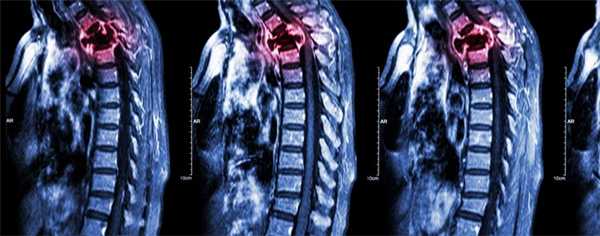

Меланома хориоидеи является новообразованием с высоким риском появления метастазов. Поэтому при обследовании пациента необходимо использовать также методы диагностики метастатических очагов: УЗИ органов брюшной полости и лимфатических узлов, рентгенографию легких, КТ, МРТ.

- Магнитно-резонансная томография.

Диагностика скелетных повреждений не сложная, но высокотехнологичная, начинают с изотопного обследования — остеосцинтиграфии, выявляющей минимальные раковые новообразования. Затем засвеченные изотопом «горячие очаги» подвергают рентгенографии или, что лучше, компьютерной томографии (КТ). ПЭТ — «королева» доказательств, к сожалению, дорогое исследование, поэтому для контроля эффективности терапии не очень подходит.